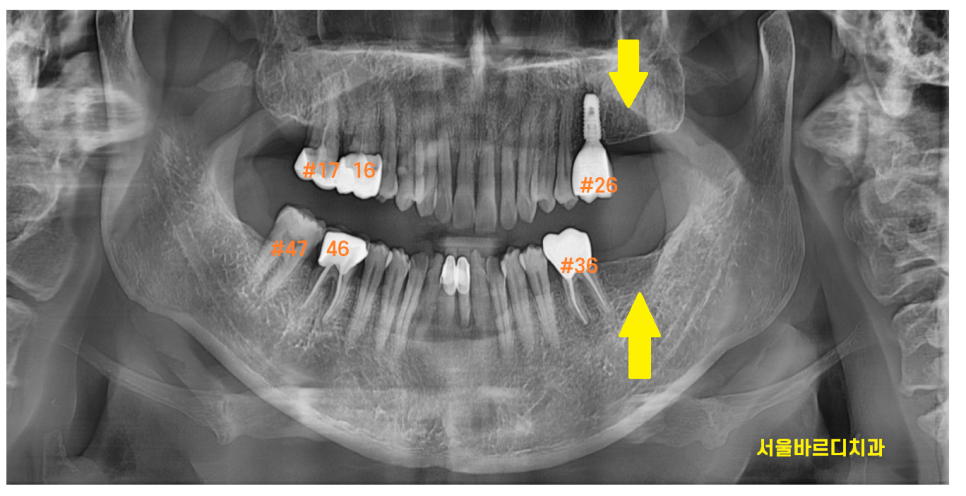

ct를 찍어 분석해보았습니다.

턱 뼈 상태는 아주 굿이었는데요.

뼈 이식을 안하고 그냥 심어도 되는 상태였습니다.

강동구 임플란트 식립 한번에 위, 아래 심는다고

계획을 말씀드렸는데요.